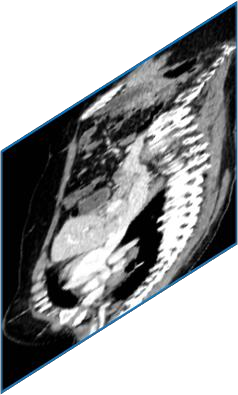

Due to the constraints of the imaging device and high cost in operation time, computer tomography (CT) scans are usually acquired with low intra-slice resolution. Improving the intra-slice resolution is beneficial to the disease diagnosis for both human experts and computer-aided systems. To this end, this paper builds a novel medical slice synthesis to increase the between-slice resolution. Considering that the ground-truth intermediate medical slices are always absent in clinical practice, we introduce the incremental cross-view mutual distillation strategy to accomplish this task in the self-supervised learning manner. Specifically, we model this problem from three different views: slice-wise interpolation from axial view and pixel-wise interpolation from coronal and sagittal views. Under this circumstance, the models learned from different views can distill valuable knowledge to guide the learning processes of each other. We can repeat this process to make the models synthesize intermediate slice data with increasing inter-slice resolution. To demonstrate the effectiveness of the proposed approach, we conduct comprehensive experiments on a large-scale CT dataset. Quantitative and qualitative comparison results show that our method outperforms state-of-the-art algorithms by clear margins.